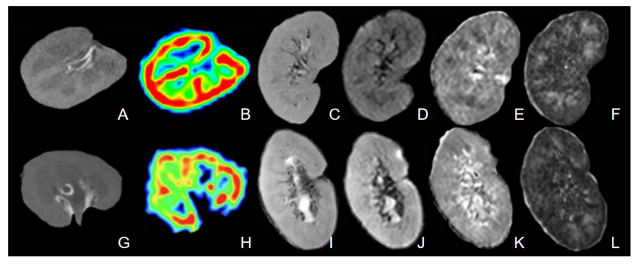

Representative images for a 26-year-old man with good allograft function and a 48-year-old man with impaired allograft function are shown in Figure 1. The RBF, ADC, FA values from patients with good renal function were higher than those from patients with impaired renal function, the difference was statistically significant (p < 0.05) (Table 1). As shown in Figure 3, there was a positive correlation between eGFR and RBF, cortical ADC, medullary ADC, cortical FA and medullary FA. RBF value had the highest AUC (AUC=0.823) to discriminate between the two groups (Table 2). The combined use of ASL and DTI showed significantly improved differential diagnosis efficacy between patients with good and impaired renal function (Figure 2).

Figure 1. Top images(A-F): axial T1WI (A), RBF maps(B), coronal T2WI(C), b0 image (D), ADC map (E), FA map (F) of a 26-year-old man with good allograft function. Bottom images(G-L): axial T1WI (G), RBF maps(H), coronal T2WI(I), b0 image (J), ADC map (K), FA map (L) of a 48-year-old man with impaired allograft function.